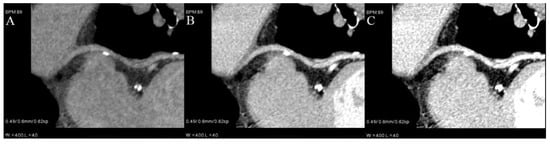

Moreover, they can be used to salvage examinations with suboptimal vessel enhancement [9,13] (Figure 3) or to asses pulmonary and coronary arteries in a single examination without an extra dose of contrast—making each coronary CTA rule out examination.

Figure 3.

Curved VMI reconstruction of coronary graft of poorly enhanced CTA. Three reconstructions with different energies ((A)—80 kev, (B)—60 keV, (C)—50 keV) and the same window and level settings. Contrast density is rising with lower energies, but also noise and artifacts from metal clips around graft.